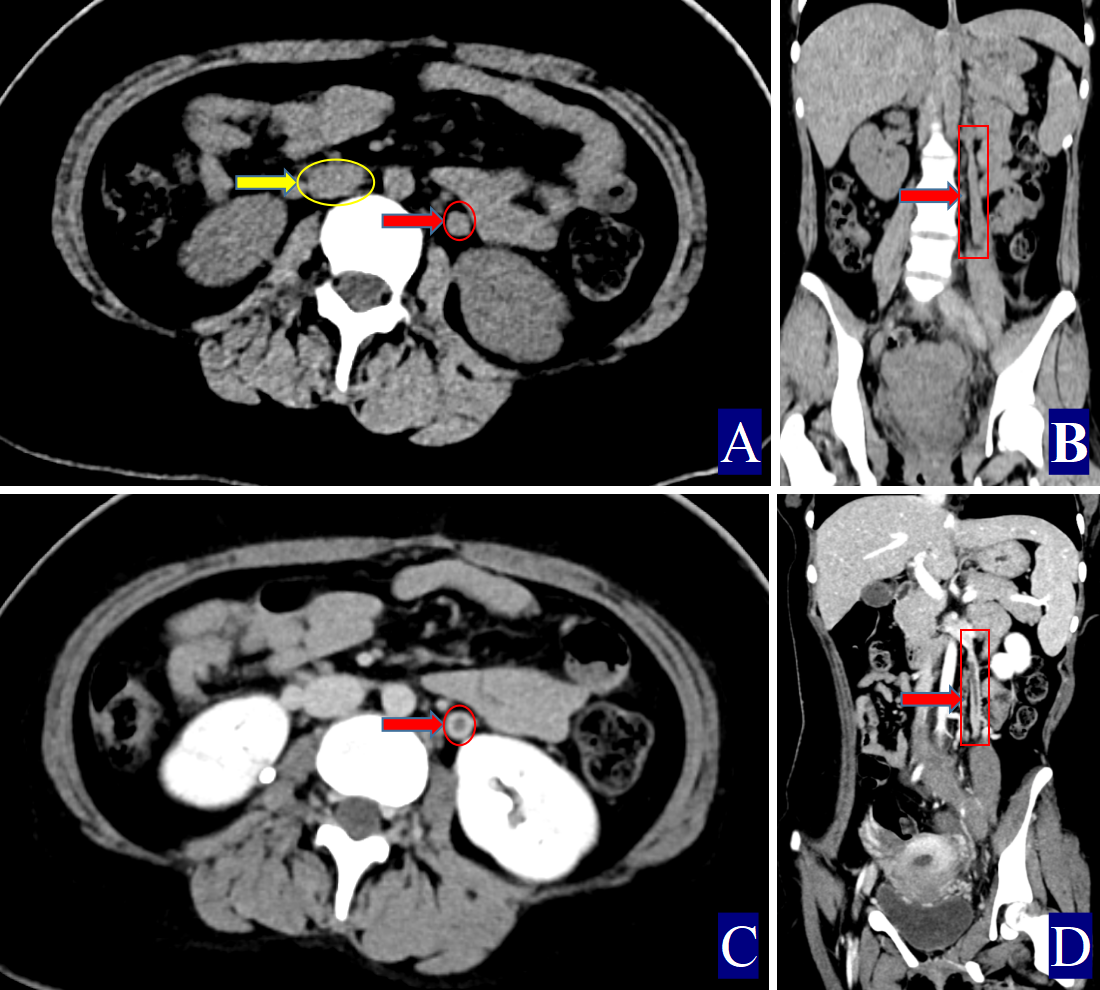

Fig. 3. The primary and secondary CT findings of ovarian vein thrombophlebitis. The red arrow indicates the ovarian vein, the yellow arrow indicates the inferior vena cava, and the green arrow indicates the periovarian vein exudate. (A) Non-contrast axial CT image. The right ovarian vein is approximately 2.92 cm wide (CT value = 63.50 HU, red arrow). The CT value of the inferior vena cava is 38.40 HU (yellow arrow), with adjacent exudation (green arrow). (B) Non-contrast axial CT image showing pelvic effusion (thick red arrow). (C,D) A 21-year-old woman with right ovarian vein thrombophlebitis and inferior vena cava thrombosi: (C) Non-contrast axial CT image. The right ovarian vein is about 1.6 cm wide (CT value = 59.30 HU, red arrow). The inferior vena cava shows a CT value of 71.80 HU (yellow arrow), and surrounding exudation is noted (green arrow). (D) Non-contrast axial CT image.

The primary CT findings of POVT included filling defects within the ovarian vein lumen along with thickening of the vessel wall (Figs. 1,2,3). Secondary signs involved pelvic effusion in 13 cases and periovarian venous exudation with increased fat density in 19 cases (Figs. 1A,C,3A,C). One patient, who developed extensive thrombosis extending to both lower extremity veins, the inferior vena cava, and pulmonary arteries, died from postpartum hemorrhagic shock. The remaining 23 patients fully recovered.

Compared with the non-POVT group, the POVT group showed significantly greater ovarian vein width on the thrombus side, higher CT attenuation of the thrombus-side ovarian vein, as well as increased CT attenuation difference and ratios (p = 0.001, Figs. 1,2,3). Using 0.90 cm as the cut-off value for ovarian vein width, the sensitivity reached approximately 91.70%, with a specificity of 95.20% (Figs. 1A,2A,3A,C,D). With 46.00 HU as the threshold for ovarian vein CT value on the thrombus side, both sensitivity and specificity were 100% (Figs. 1A,2A,3A). For a CT attenuation difference cut-off of 12.50 HU, the sensitivity was 95.30%, and specificity remained 100%. Similarly, a ratio cut-off of 1.1 yielded a sensitivity of 95.30% and specificity of 100% (Figs. 1A,2A,3A).

In one POVT case involving extensive inferior vena cava thrombosis, the CT value of the inferior vena cava exceeded that of the ovarian vein, resulting in a negative CT attenuation difference of –12.50 HU and a ratio of 0.83 (Table 1; Fig. 3C,D).

Direct signs observed on CT included variable widening of the ovarian vein, increased intraluminal density, and filling defects, often accompanied by vessel wall thickening, which is in line with prior reports [16, 17, 18, 19, 20, 21] (Figs. 1,2,3). A notable finding in our study was the identification of previously undescribed indirect signs: increased fat density around the ovarian vein in the pelvis and the presence of small-volume pelvic effusion (Figs. 1A,3A–D). These signs may reflect the local inflammatory reaction associated with thrombophlebitis.

Semi-quantitative parameters from non-contrast CT scans revealed clear differences between the POVT and non-POVT groups. The thrombus-side ovarian vein width, CT attenuation of the thrombotic ovarian vein, the difference between ovarian and inferior vena cava CT values, and their ratio were all significantly higher in the POVT group (p = 0.001, Figs. 1,2,3). These parameters may serve as reliable diagnostic references. For instance, using 0.90 cm as the cut-off for ovarian vein width yielded a sensitivity of approximately 91.70% and a specificity of 95.20%. This supports earlier findings [5] that vein enlargement is a key feature of POVT (Figs. 1,2,3). A CT attenuation cut-off of 46.00 HU for the thrombotic ovarian vein achieved 100% sensitivity and 100% specificity (Figs. 1,2,3). Similarly, a CT attenuation difference threshold of 12.50 HU and a ratio cut-off of 1.1 also demonstrated strong diagnostic performance (Figs. 1,2,3). However, in one patient with extensive thrombosis of the inferior vena cava, the ovarian vein had a lower CT value than the cava, resulting in a negative difference (–12.50 HU) and a ratio of 0.83, reflecting variability in advanced or complex cases. Currently available non-invasive diagnostic tools for POVT include Doppler ultrasound (sensitivity 52%), magnetic resonance imaging (MRI) (92%), and contrast-enhanced multidetector CT (100%) [5]. The present study indicates that non-contrast CT semi-quantitative parameters can closely match the diagnostic accuracy of enhanced CT, while offering greater simplicity, lower cost, and avoiding the risks associated with contrast agent use.